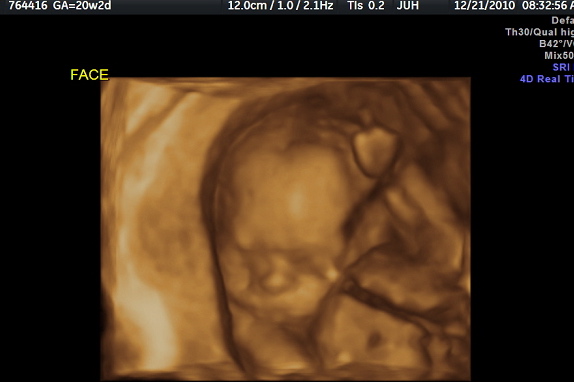

Best moment this week: Last week at 20 weeks 2 days we got to see NBC via ultrasound. Two days after our ultrasound I had a regular OB appoint where I got to hear the heart beating nice and strong (when she could find it as NBC was moving around like crazy). Nothing could have made my week much better than seeing and hearing my sweet lil baby. Or at least I thought nothing could have made it much better, but then on Christmas Eve I felt the baby move from the outside. This week Adam got to feel the baby kick his hand. What pure joy came across Adam's face when he felt the sudden kick!

Gender: The ultrasound tech is the only one that knows. Can’t wait to do a couple wives tales and then have A tell me if we have a son or daughter on NBC’s birthday! Oh I just get goose bumps thinking about it!

Milestones: Having our big ultrasound. Feeling movement from the outside.

I had a regular OB appointment last Thursday, where I got to hear NBC’s heart beating. However the lil one kept moving all around, which made it hard for the dr to find it with her Doppler. He/she’s a very active little machine! Here are the quick highlights from the appointment:

Baby weight: 11 oz

Baby Heartbeat: 130’s